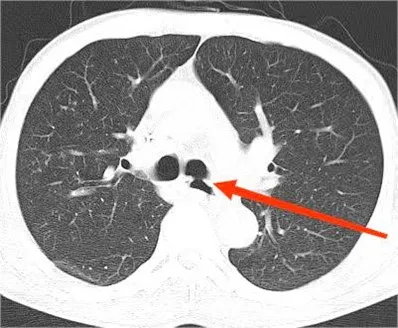

患者,男,61岁,确诊食管癌1月余,入住我院肿瘤科。入院时患者吞咽困难,进食时频繁呛咳,咳嗽、咳痰症状严重,同时营养状也急剧恶化。完善胸部CT及电子支气管镜检查,明确诊断为气管食管瘘,食管肿瘤坏死后穿透左主支气管膜部,形成异常瘘道。

▲术前胸部CT(箭头指向为气管食管瘘口)